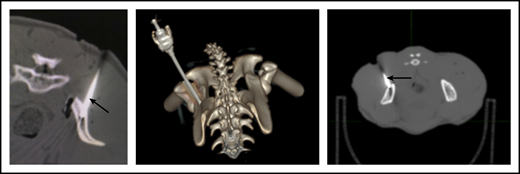

To ensure that CD34+ cells were injected directly into the IB space, CT imaging confirmed correct placement of the BM biopsy needle in all experiments. (Figure 2). To examine the retention of OIB-delivered cells in RMs, 89Zr-oxine labeled CD34+ cells were injected using the OIB technique (controlled infusion rate, <0.2 mL/min; total volume, <5 mL). Serial imaging with PET/CT was performed after cell transfer to quantify the proportion of labeled cells at each anatomical site, as a percentage of injected dose of the radioisotope. Figure 3 confirms retention of CD34+ cells at the site of injection immediately (10 minutes posttransfer corresponding to the midpoint of a 20-minute scan) after injection using the OIB technique. At 1 hour after OIB injection, 78% of the injected cells localized to the injection site, that is, remained in the right iliac IB space. Approximately 15% of infused cells leaked from the iliac IB space after IB injection and distributed to other organs, notably the liver and spleen, with the remaining radioactivity (∼7%) detected mainly in the kidneys and bladder, consistent with deferoxamine chelation and urinary excretion of free 89Zr.

CT imaging confirming successful localization of the BM needle (arrowed) into the RM right posterior superior iliac crest. Following 10-Gy TBI, RM were anesthetized, and a BM needle was placed into proper position in the IB marrow space prior to CD34+ cell infusion.